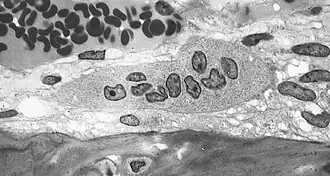

Резорбция костной ткани (разрушение, рассасывание кости, остеолиз) происходит при участии гигантских многоядерных клеток, так называемых остеокластов, которые также имеют большое количество лизосом, митохондрий и вакуолей.

Остеокласт — это основная клетка, участвующая в процессе резорбции кости. При активизации этих клеток у них появляется функциональная зона — «гофрированный край», или «щёточная каёмка». Гофрированный край представляет собой спирально-скрученную мембрану клетки с множественными цитоплазматическими складками, он обращён в сторону развивающегося процесса резорбции и является местом активного окисления тканей.[1]:26-28 Группа остеокластов растворяет минеральный компонент кости, а также гидролизует органический матрикс. Разрушение кости начинается с прикрепления остеокласта к минерализованной костной поверхности «гофрированным краем», через который выделяются гидролитические ферменты и протоны, а также различные интегрины (α₁, αᵥ, β₁, β₃), участвующие в растворении кости.[1]:28 Другие клетки, принимающие участие в резорбции костной ткани — это моноциты и макрофаги. Они взаимодействуют с костной тканью посредством фагоцитоза и хемотаксиса, в большинстве случаев действуя как «уборщики мусора». Помимо фагоцитарной активности продуцируются цитокины (ИЛ-1, ИЛ-1α, ИЛ-1β, ФНО-α и др.) влияющие на активизацию коллагеназ, разрушающих белковый матрикс. Кроме того, моноциты и макрофаги рассматриваются многими учёными как предшественники остеокластов.[1]:31-32 Имеются сведения о влиянии лимфоцитов на резорбцию костной ткани посредством секреции ФНО-β, а также через 1,25-дигидроксивитамин D и ПТГ, к которым лимфоциты имеют рецепторы.[1]:32